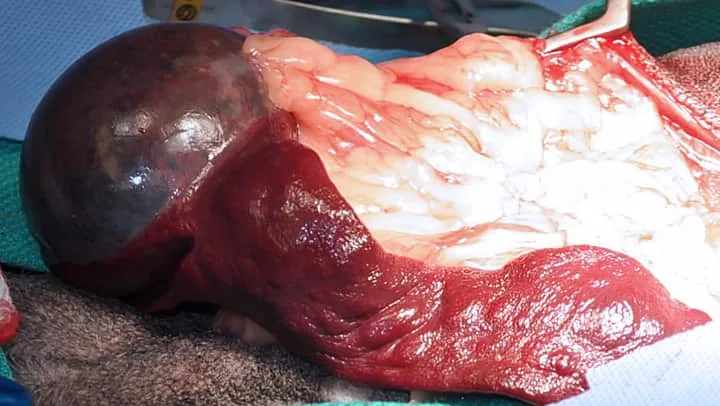

Splenic masses are commonly treated with splenectomy. In most cases, the tumor type is not known at the time of surgery. In the absence of a hemoabdomen, an ultrasound-guided fine-needle aspirate can be performed to determine tumor type of a solid mass. In cases of cavitated masses, with or without hemoabdomen, aspiration is a low-yield, potentially dangerous test and is not recommended. In the author’s opinion, if a small (<2-cm), noncavitated splenic mass is found as an incidental finding on abdominal ultrasound, close monitoring may be appropriate. Ultrasound should be repeated in a month, and splenectomy should be recommended if the mass is progressive. In most other cases, splenectomy to prevent rupture of the mass and hemoabdomen is recommended. If the patient is presented with a hemoabdomen, the splenectomy is an emergency (Figure 5). Staging should be performed with a minimum of 3-view thoracic radiographs and abdominal ultrasound (or thoracic and abdominal CT scan).

Splenic mass without hemoabdomen

Hemangiosarcoma is the most common malignant tumor of the spleen,15 but it is important to remember that not all splenic tumors are malignant. If the final diagnosis is hemangiosarcoma, the long-term prognosis for survival is poor, although adjuvant therapy may prolong survival.15